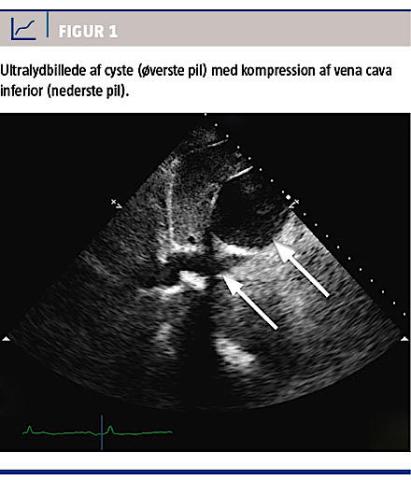

På mistanke om samtidig lungeemboli blev der udført ekkokardiografi, der ikke viste tegn til højresidig belastning. Man observerede en stor levercyste, der afklemte VCI få cm fra indmundingen til højre atrium (Figur 1).